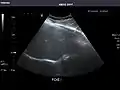

Liver: Diffusely homogeneous and normal in echogenicity. No focal mass or contour nodularity. No intrahepatic biliary ductal dilatation.

Portal Vein: Patent main portal vein.

Gallbladder: No stones, wall thickening, or pericholecystic fluid.

Common Bile Duct: Nondilated measuring 1.3 mm at the level of the porta hepatis.

Pancreas: Visualized portions unremarkable.

Spleen: Normal in size.

Kidneys: Right and left kidneys measure 11.5 cm and 12 cm in length respectively. No hydronephrosis. Small left lower pole kidney cyst.

Ascites: None.

Aorta: Visualized portions normal in caliber, 16 x 15 mm.

IVC: Normal.

IMPRESSION:

Normal abdominal ultrasound.